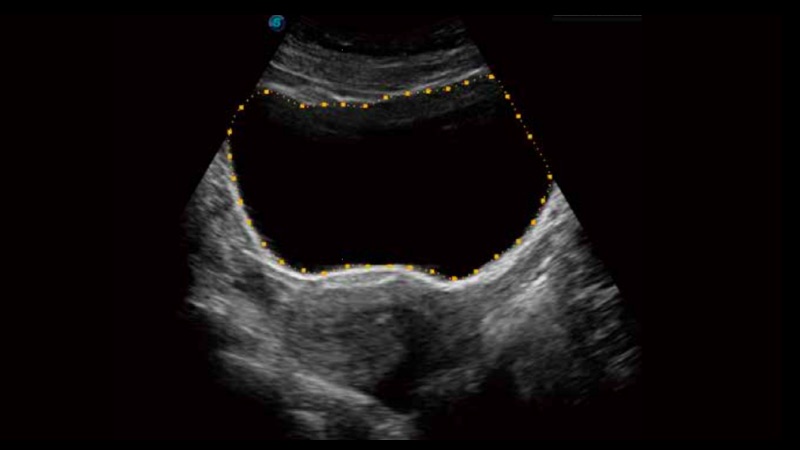

膀胱自動(dòng)測(cè)量,一鍵式膀胱壁追蹤和容量測(cè)量可有效提供更精確的輪廓和結(jié)果,不受膀胱形狀和大小的影響。